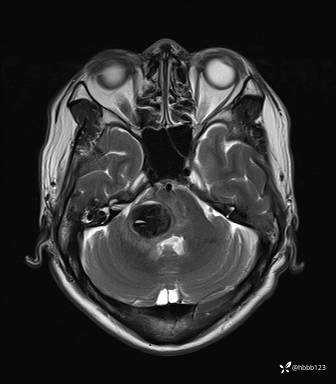

患者男,51岁。

简要病史:患者自述于1周前至某人民医院发现脑干肿瘤(具体不详),为求进一步诊断至我院就诊。

完善颅脑MRI平扫+增强,颅脑CT平扫:

T2: